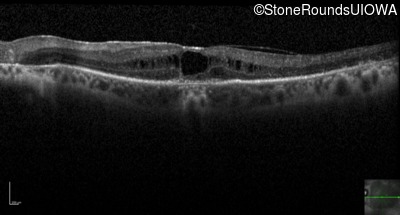

Optical Coherence Tomography - Left - 20/125 +2

Exemplar / OCT Stack